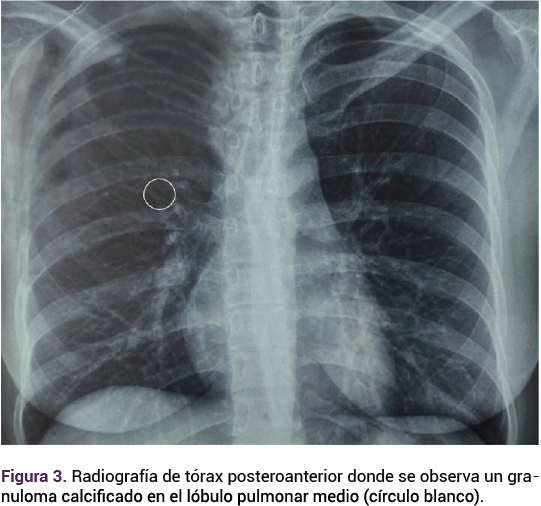

En el ultrasonido transvaginal el ovario izquierdo se observó aumentado de tamaño, con varias cavidades anecoicas y septos de grosor moderado a grueso, volumen de 45.9 cc. Al Doppler color, con evidente vascularización en los septos y paredes internas, con flujo de moderada a alta resistencia, clasificación O-RADS 4 con riesgo intermedio de malignidad (Figura 2). El ovario derecho mostró una imagen quística, con centro sólido en su interior, volumen de 28.1 cc. Serología de VIH, sífilis y hepatitis B y C negativas. La radiografía de tórax con granuloma pulmonar calcificado de 5 mm en el lóbulo pulmonar medio derecho. Figura 3

<strong>Figura 3</strong>

Figura 3.

La tuberculosis ovárica es una forma poco frecuente de manifestación de tuberculosis extrapulmonar, casi siempre originada por reactivación o diseminación de forma hematógena de un sitio extra genital, que puede ocurrir sin evidencia clínica o infección en ese sitio.13 La paciente del caso tenía antecedente de tuberculosis pulmonar activa, debido a un granuloma calcificado advertido en la radiografía de tórax que sugirió una infección previa o latente.14